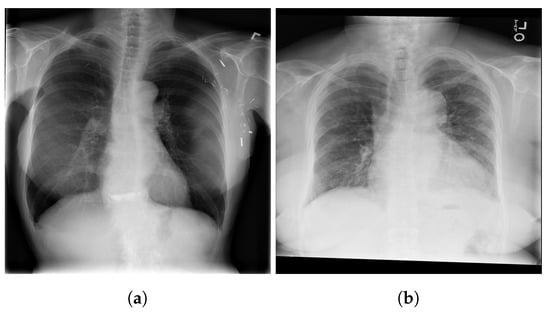

6. Model Limitations